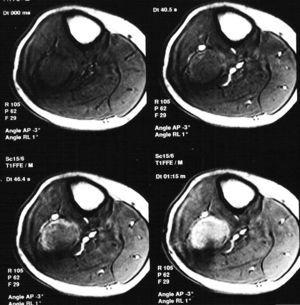

Paciente varón de 15 años, que fue remitido a consultas de traumatología por genu valgo. No tenía antecedentes de interés, salvo crisis asmáticas en la infancia, y la presencia de una lesión lítica ya conocida en el peroné, que sugería el diagnóstico diferencial de displasia fibrosa o quiste óseo aneurismático como primeras posibilidades. La lesión parecía haber crecido respecto a estudios previos. En la radiografía simple (fig. 3), se identificaba una gran lesión lítica expansiva que afectaba predominantemente a la metáfisis proximal del peroné derecho, extendiéndose caudalmente a la diáfisis, y limitada superiormente por la placa de crecimiento. No tenía matriz ósea interna y la zona de transición, al menos en la zona inferior, era estrecha. En el interior presentaba un patrón de múltiples septos con cierto adelgazamiento endostal. En la TC (fig. 4) la cortical estaba muy adelgazada, con focos de discontinuidad sin identificar masa de partes blandas, y presentaba finos septos internos. Se realizó un estudio mediante RM con un equipo de 1,5T (Gyroscan Philips Intera). En la RM el tamaño aproximado de la lesión era de 8,5 x 3,3 x 3 cm (craneocaudal x anteroposterior x lateromedial). La lesión insuflaba el peroné sin visualizar masa de partes blandas. En la secuencia T1-ES (TR/TE 460/15) se comportaba hipointensa de forma homogénea (fig. 5). En la secuencia STIR (1688/15) (fig. 6) parecía tener dos componentes, con diferentes intensidades de señal. El superior hipointenso y el inferior levemente hiperintenso. En la secuencia dinámica T1 (TR/ TE 460/15) tras gadolinio itravenoso (figs. 7 y 8) presentaba un leve realce periférico del componente superior en fase tardía con prácticamente nulo realce en fase precoz y, sin embargo, un intenso realce del componente inferior en fase precoz, seis segundos después de que el contraste se identificase en el interior de los vasos arteriales, con realce persistente en fase tardía (fig. 9). Se realizó una gammagrafía ósea de cuerpo completo en proyecciones anterior y posterior en tres fases. En la fase vascular se observaba un incremento en la llegada del radiotrazador del pool sanguíneo a la región proximal del peroné derecho. La imagen tardía mostraba una hipercaptación en el extremo proximal de dicho hueso. Descartaba la posibilidad de quiste óseo, que no suelen mostrar captación en la gammagrafía y aconsejaban descartar otro tipo de tumoración ósea. No se visualizaron otras lesiones a distancia. En estos momentos el diagnóstico diferencial propuesto fue de fibroma condromixoide, fibroma desmoplásico y quiste óseo aneurismático, a pesar de la ausencia de niveles líquido-líquido. A continuación se realizó una biopsia abierta, con diagnóstico de fibroma desmoplásico. En el estudio macroscópico se identificaban varios fragmentos blanquecinos de consistencia ósea. En el estudio microscópico, se identificó una proliferación de células elongadas, separadas de abundantes fibras de colágeno. La densidad celular era muy variable en función del campo estudiado, lo mismo que la disposición de las fibras de colágeno, bien onduladas o con gran laxitud. Las células tenían núcleos ovoideos, sin aparentes nucleolos y sin figuras mitóticas. Algunos de los remanentes óseos atrapados en la muestra tenían actividad osteoclástica, sin ver en ningún momento atipias.

Fig. 7.--Secuencia dinámica T1-ES tras la administración de gadolinio intravenoso de la vertiente superior de la lesión. Leve realce periférico en fase tardía con ausencia de realce significativo en fase precoz. Se visualiza el trayecto de la biopsia.

Fig. 8.--Secuencia dinámica T1-ES tras la administración de gadolinio intravenoso de la vertiente inferior de la lesión. Marcado realce en fase precoz.

Fig. 9.--Secuencia coronal T1 con supresión grasa tras la administración de gadolinio intravenoso en fase tardía. Realce homogéneo de la vertiente inferior de la lesión y realce periférico de la superior.

La RM permite una clara delimitación entre el hueso normal y el tumoral. Generalmente aparece hipointenso tanto en las secuencias T1 como T2, como los linfomas o los tumores fibrosos, debido a la densa matriz conectiva, y para algunos autores debido a la relativa hipocelularidad, lo que significa una disminución de los protones móviles6. Otros autores recogen otros hallazgos, como la presencia de una pseudocápsula, focos de necrosis, niveles líquido-líquido dentro del tumor8 y, en ocasiones, un comportamiento hiperintenso en las secuencias T22,4. En nuestro caso se identificaban dos componentes diferentes dentro de la misma lesión de diferente señal en las secuencias T2. El componente superior es hipointenso y el inferior de intensidad intermedia. En las secuencias dinámicas postgadolinio intravenoso, el componente superior mostraba un leve realce periférico en fase tardía con prácticamente nulo realce en fase precoz y el componente inferior presentaba intenso realce en fase precoz, que persistía en fases tardías.